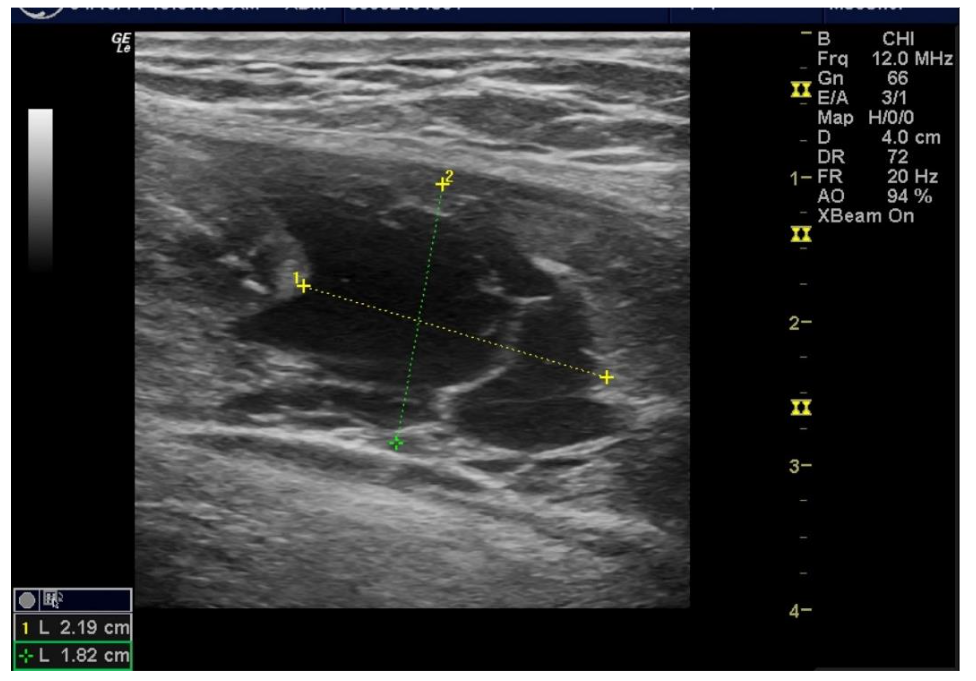

Figure 7A: Pre-Treatment Medial Meniscal/MCL Damage and Inflammatory Changes. Figure 7B: Painful Meniscal/LCL ultrasound image outcome at 10 months BC treatment. tSVF + HD PRP (5.5X) (70% tSVF/30% HD PRP. NOTE: Improvement of lateral meniscal/LCL areas without residual pain or dysfunction.